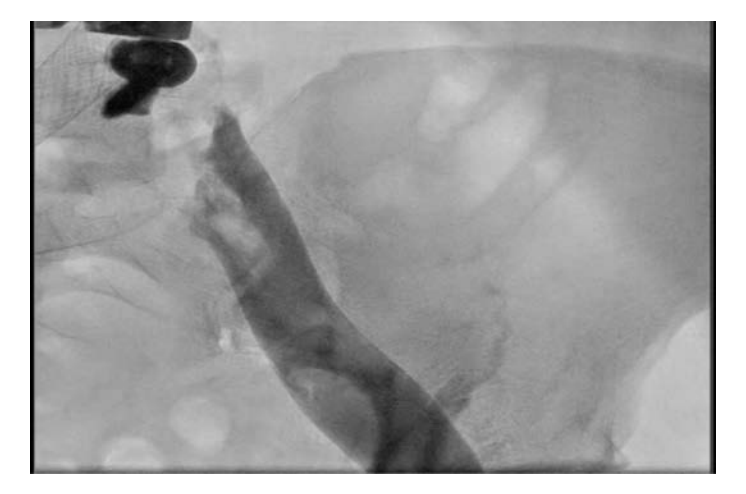

The patient was placed in a prone position and access via the ipsilateral right popliteal vein was obtained. A Destination sheath (Terumo) was advanced over a Wholey wire (Medtronic) to the area of the thrombus (Figure 1). The wire was advanced through the occluded thrombus in the right CIV, with care taken in order to avoid entering through the contralateral stent struts that extended into the IVC. Intravascular ultrasound (IVUS) was used to confirm the location of the wire between the wall of the IVC and the Wallstent (Figure 2).